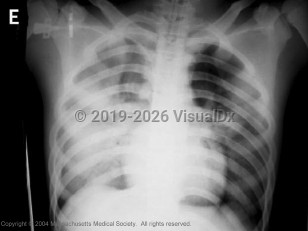

Atypical presentations of avian influenza have been reported. Patients have developed nausea, vomiting, and diarrhea preceding acute respiratory failure. Progression to acute respiratory distress syndrome (ARDS) and respiratory failure is common. Complications have included bacterial sepsis, pulmonary hemorrhage, and multi-organ failure. The mortality rate of hospitalized patients has been high due to progressive respiratory failure.